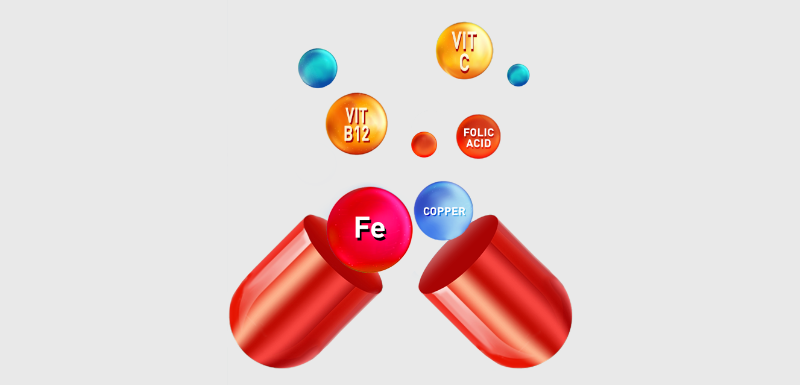

Supports Optimum Blood Health

With proper diet and exercise

Multi-vitamins + Minerals

Multivitamins + Iron + Calcium

Iron + Folic acid

Iron + Vitamin B Complex